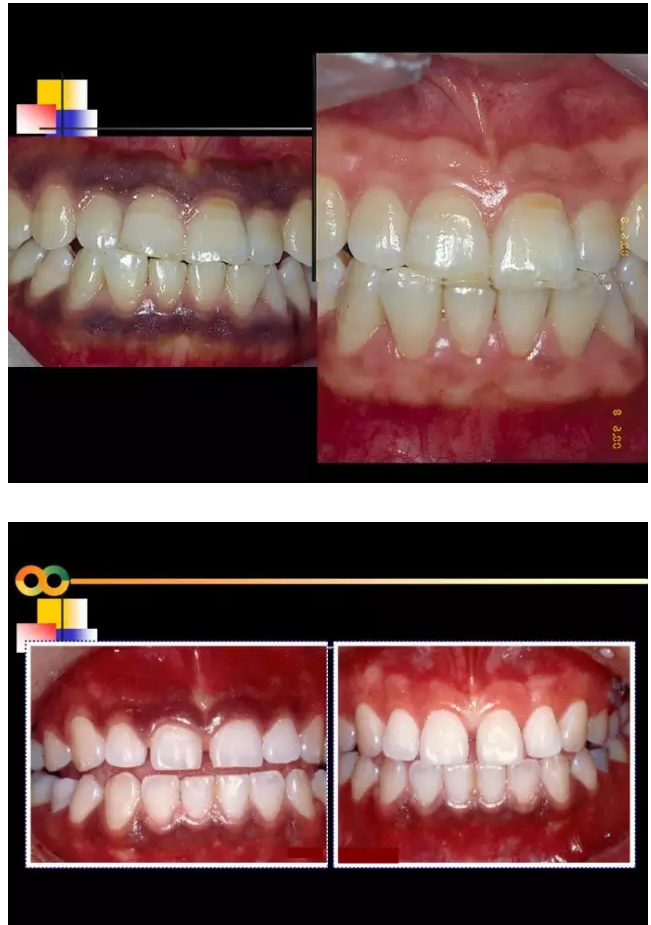

相關(guān)牙周防治